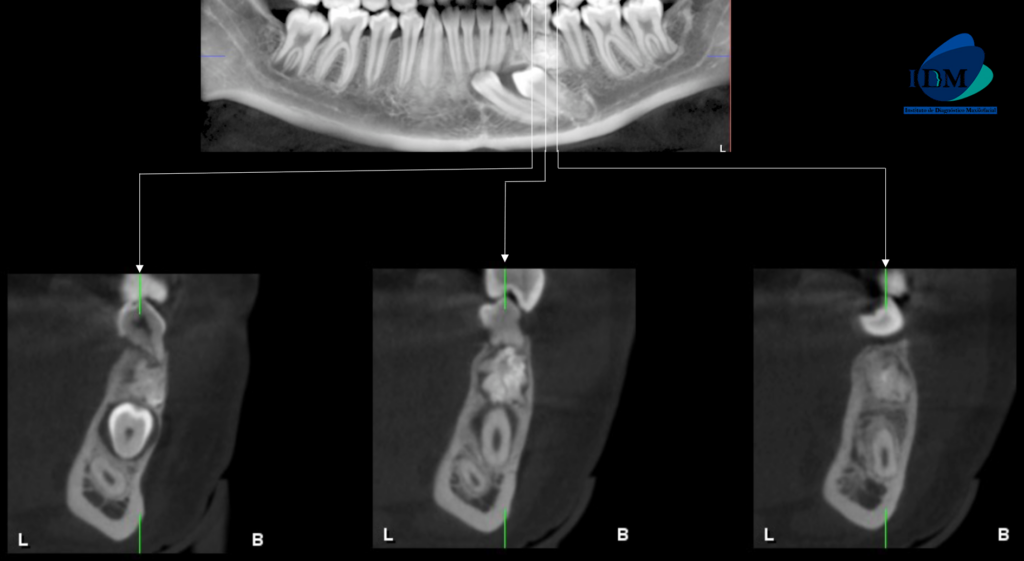

En las reconstrucciones 3D se representa de manera didáctica Odontoma compuesto y complejo (Figura 4).

RECONSTRUCCIÓN 3D